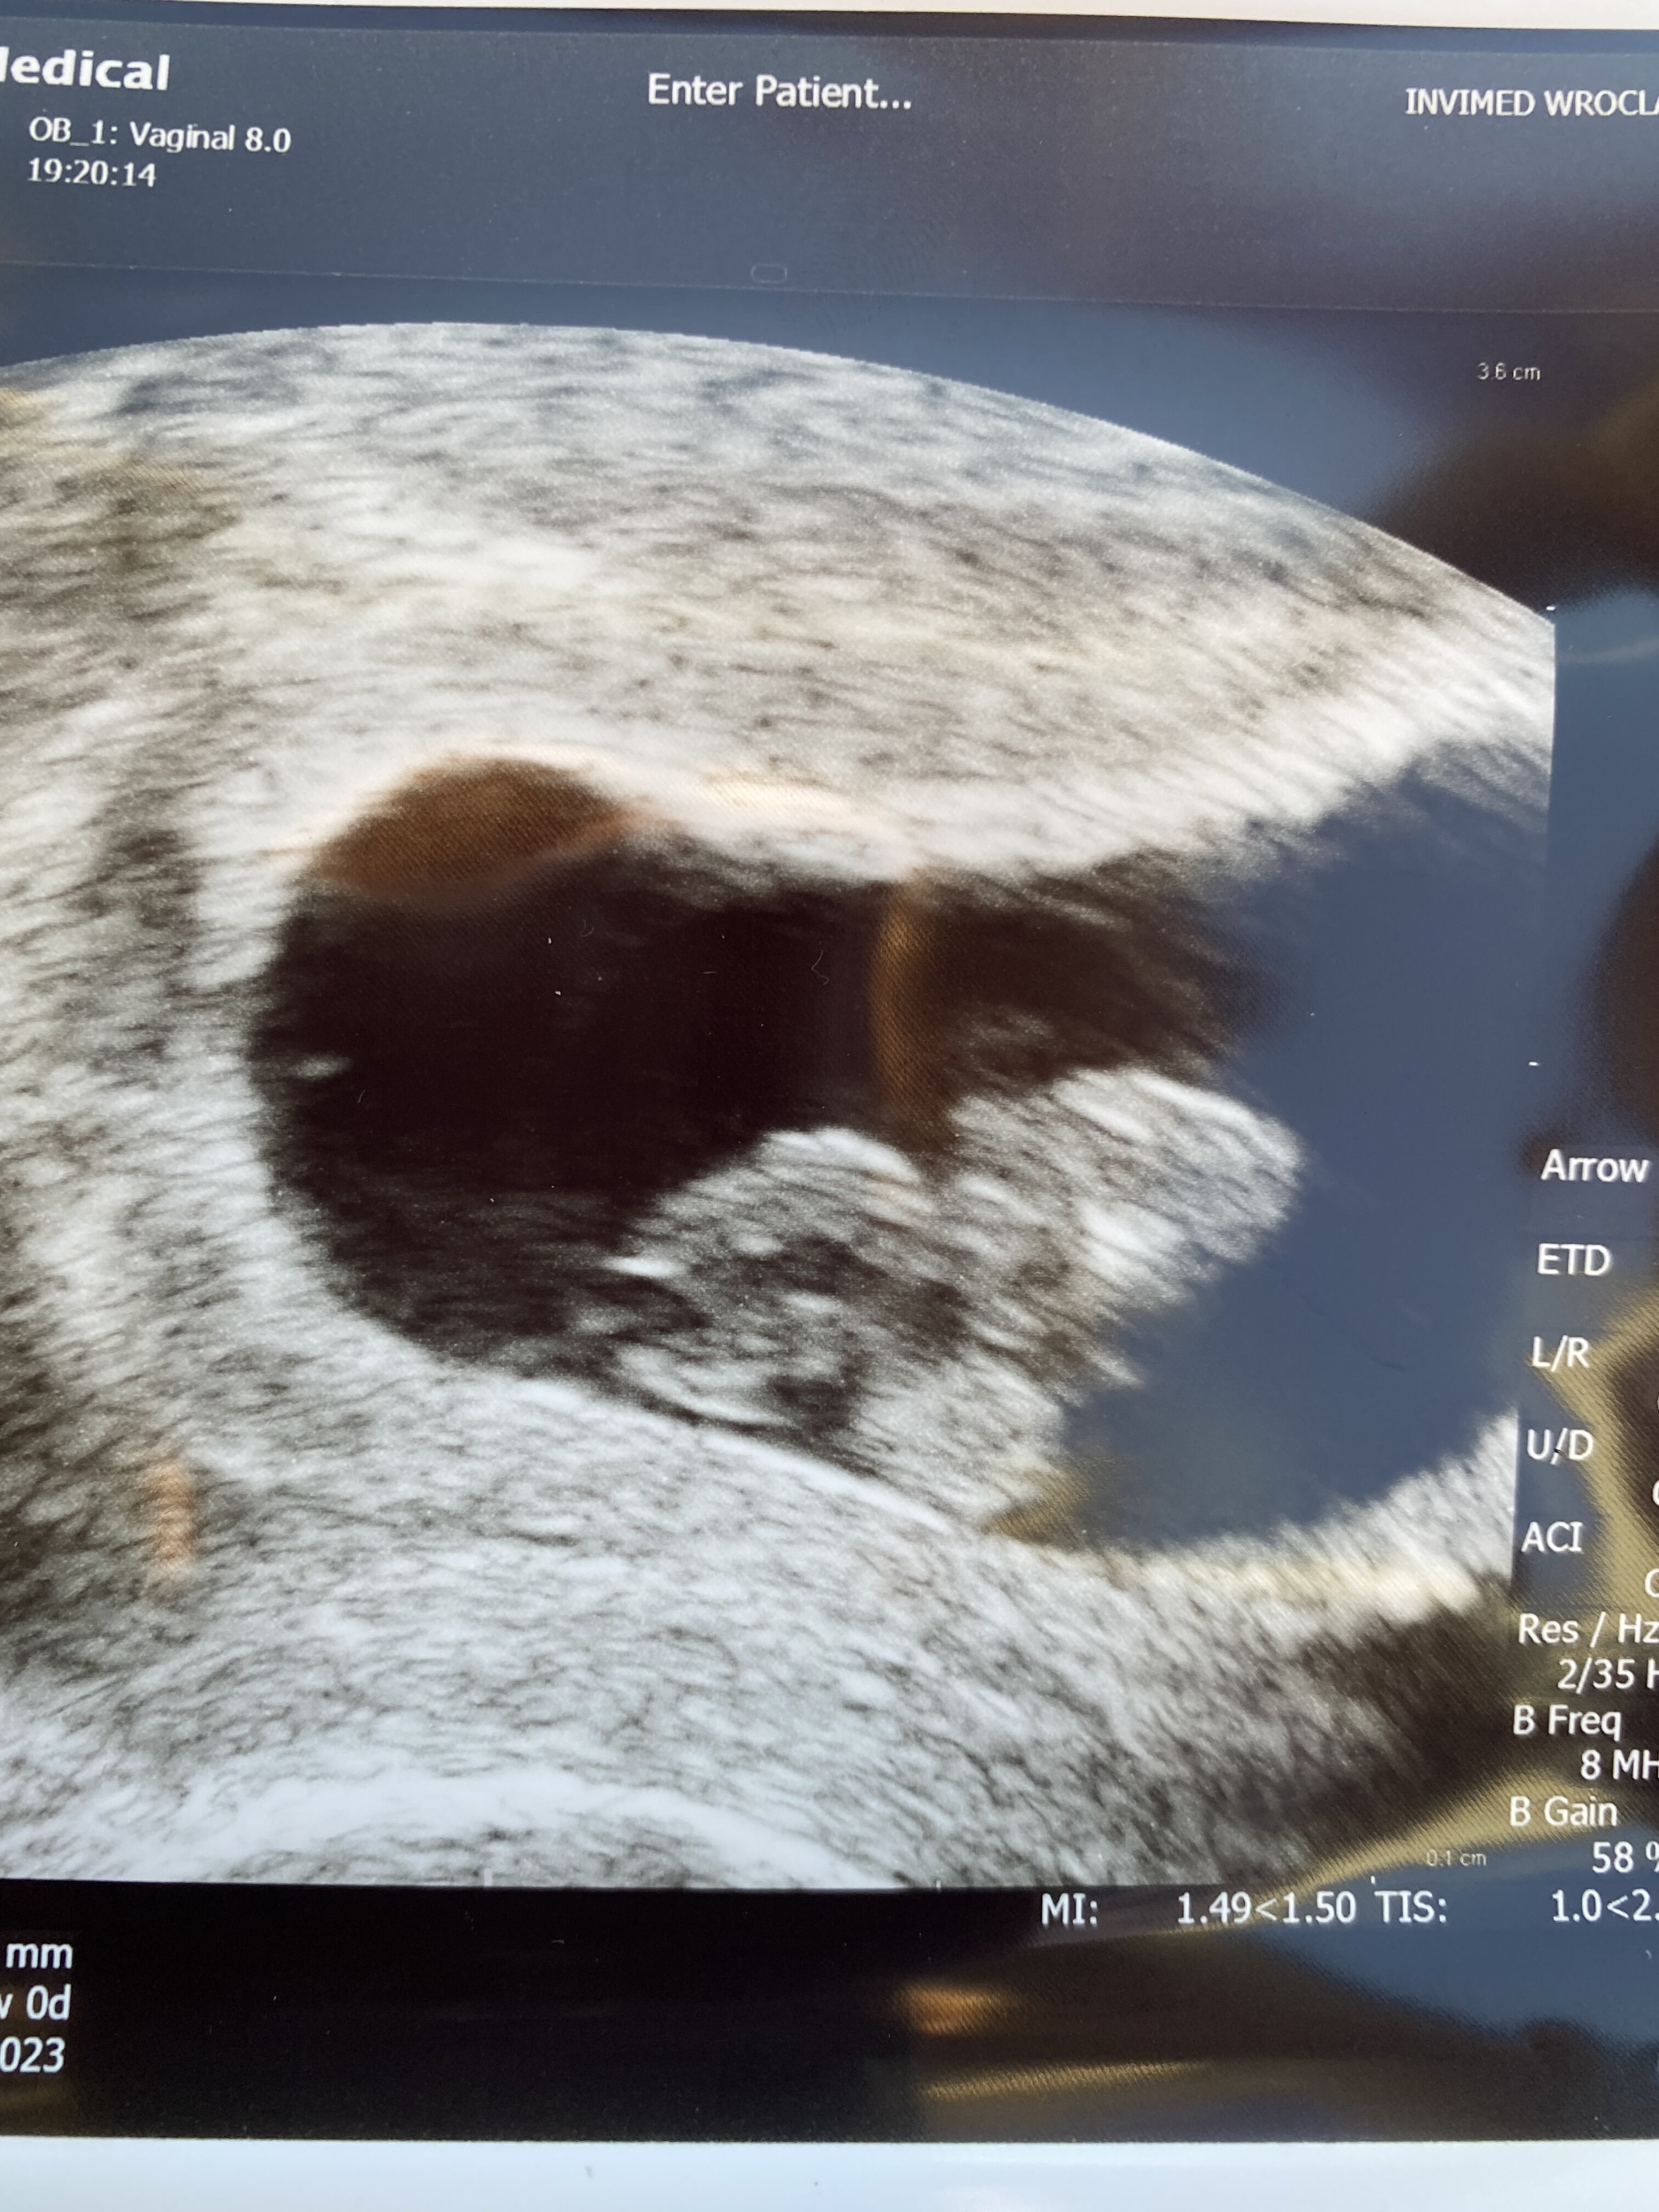

Super super super !!! Zazdrościmy tych widoków.Kochane udało się !! Serduszko bije!Maleństwo ma 8tygodni i 15,7mm

Dziekuje wam wszystkim za wasze wsparcie i dodanie siły w tym trudnym oczekiwaniu !! Jesteście niezastąpienione! Oby dalej wszystko dobrze się układało..